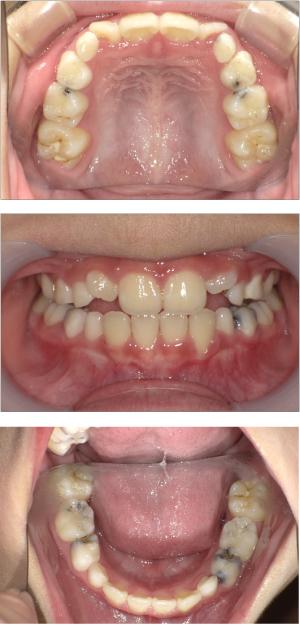

バイオブロック矯正(顎顔面口腔育成治療)

矯正治療は大人になって始めるよりも子どもの頃から始めた方が確実に良い結果をもたらします。成長が盛んな子供の時期に、顎や顔の成長を利用しながら治療ができる大きなメリットがあるからです。当院では、非抜歯矯正を推奨しておりバイオブロック矯正を取り入れています。

バイオブロック矯正の考え方は歯並びが悪くなる原因にアプローチする治療法になります。

舌の位置や口呼吸から乱れてしまった下顎の後退を正し、顎顔面が本来あるべき位置へと誘導させていく治療です。

- 歯並びの改善